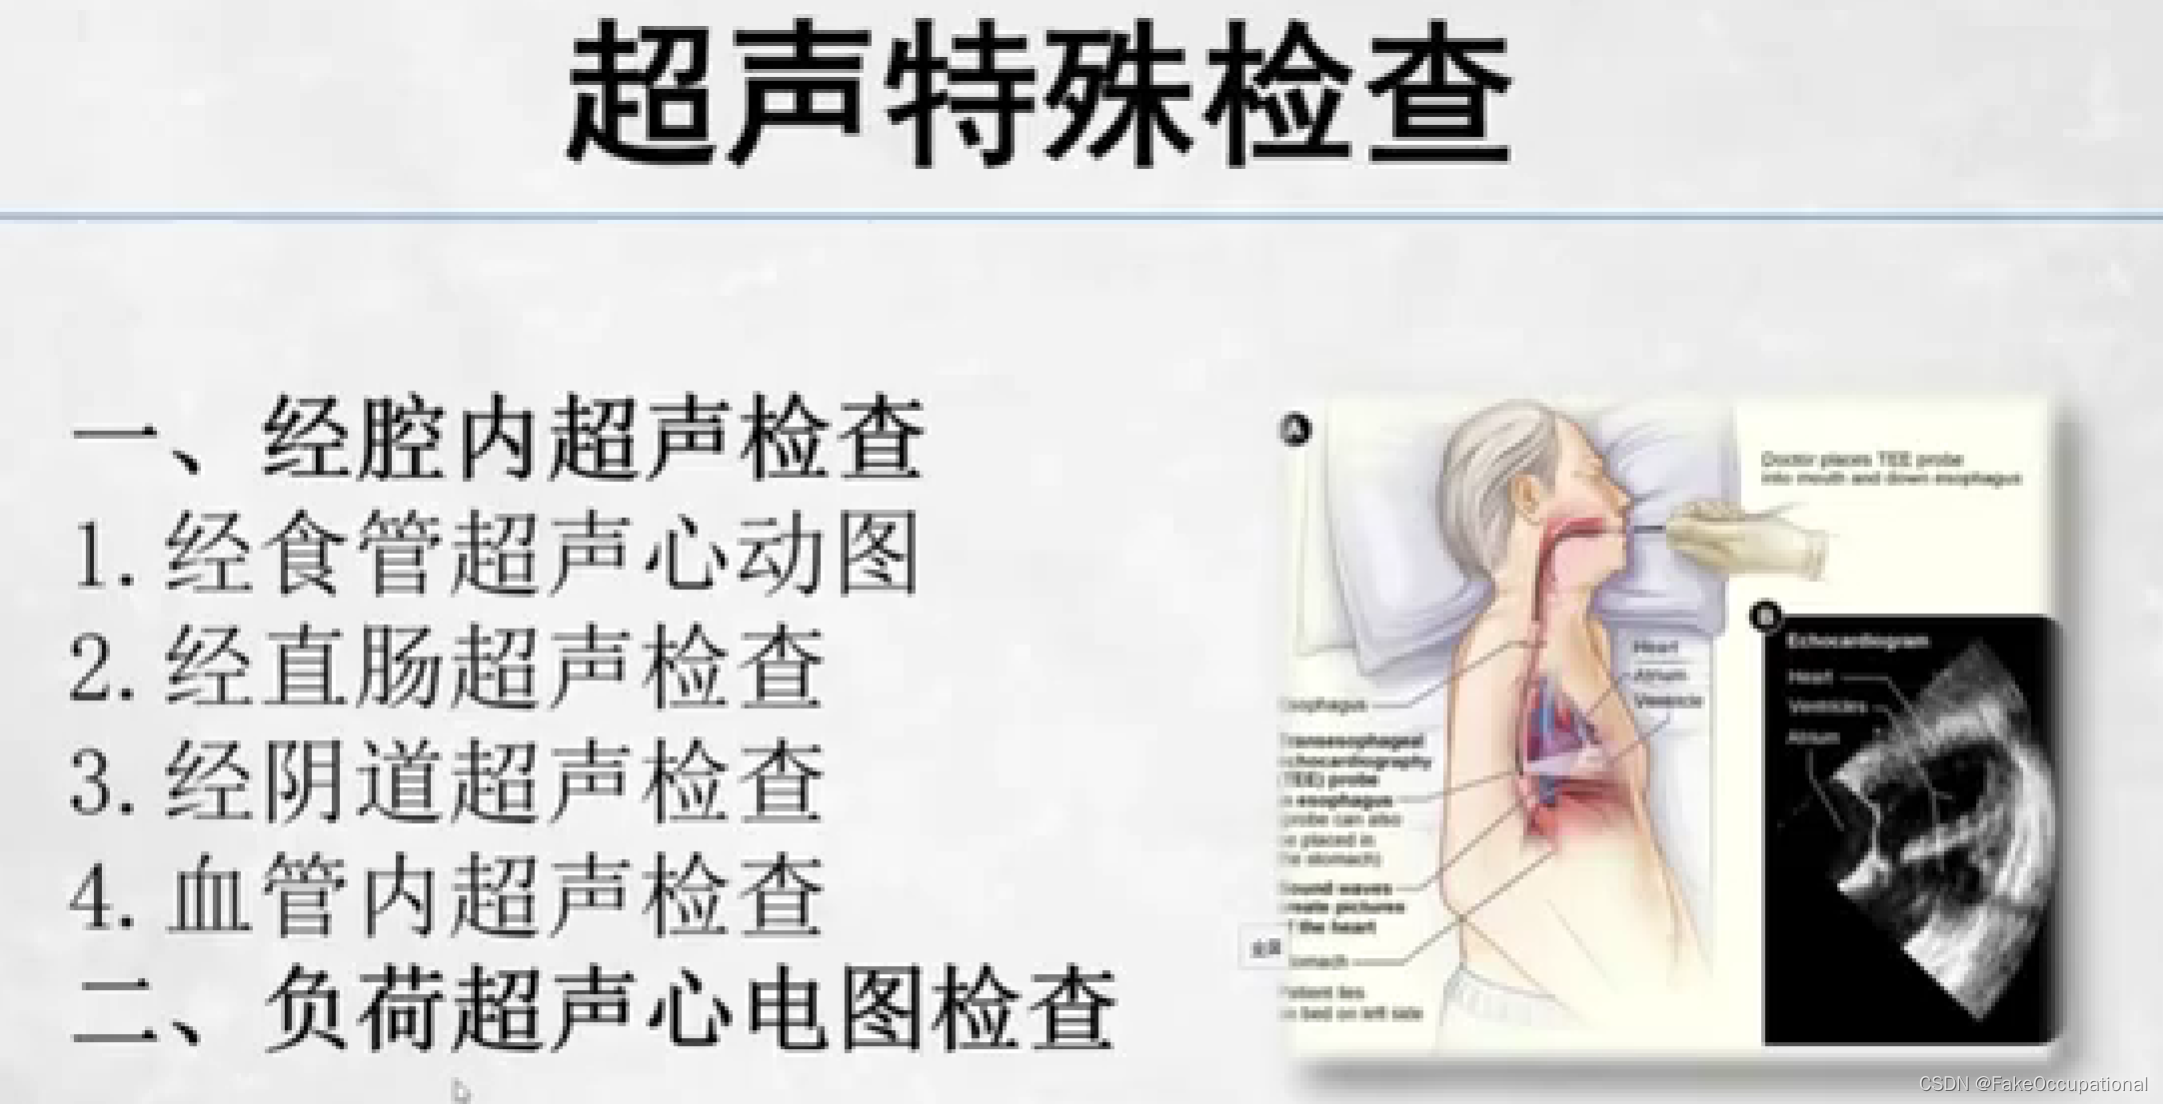

超声特殊检查与新技术

超声新技术

1.三维超声

2.超声造影

3.弹性成像

4.斑点追踪超声心动图

5.声学定量

6彩色室动态分析

7.超声组织定征